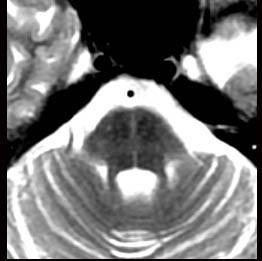

问题 患者,男,55岁,渐起出现直立时头昏,直立性低血压2年,近半年出现眼球震颤、构音困难、步态不稳、共济失调、震颤及精神异常等症状,头颅MRI如图示,可采用的治疗方法为 ( )

选项 A、使用α受体拮抗剂盐酸米多君 B、使用钙离子拮抗剂尼莫地平等 C、床上坐起或下地时应快速 D、穿弹力紧身衣裤和弹力长袜 E、平卧时适当抬高头部 一、多项选择题

答案 ADE